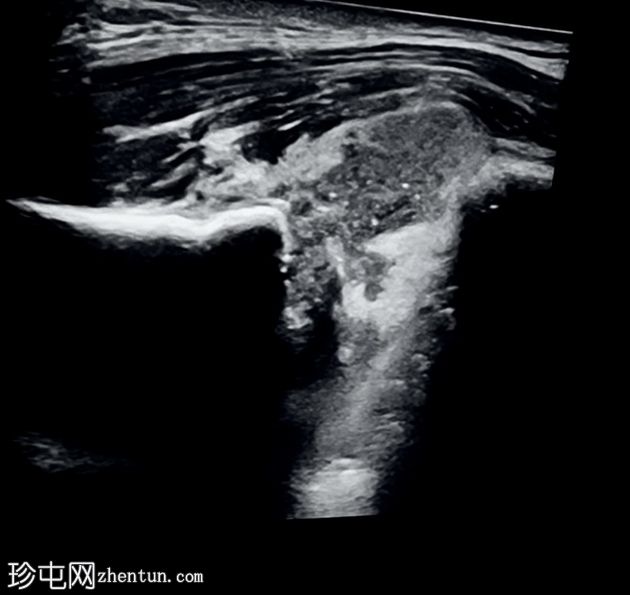

超声

横断面

斜位

超声显示胸锁关节内有异质性低回声区,内含碎屑,周围软组织炎症,符合积液的影像学表现。

病例讨论

影像学特征符合非糖尿病患者的胸锁关节化脓性关节炎。